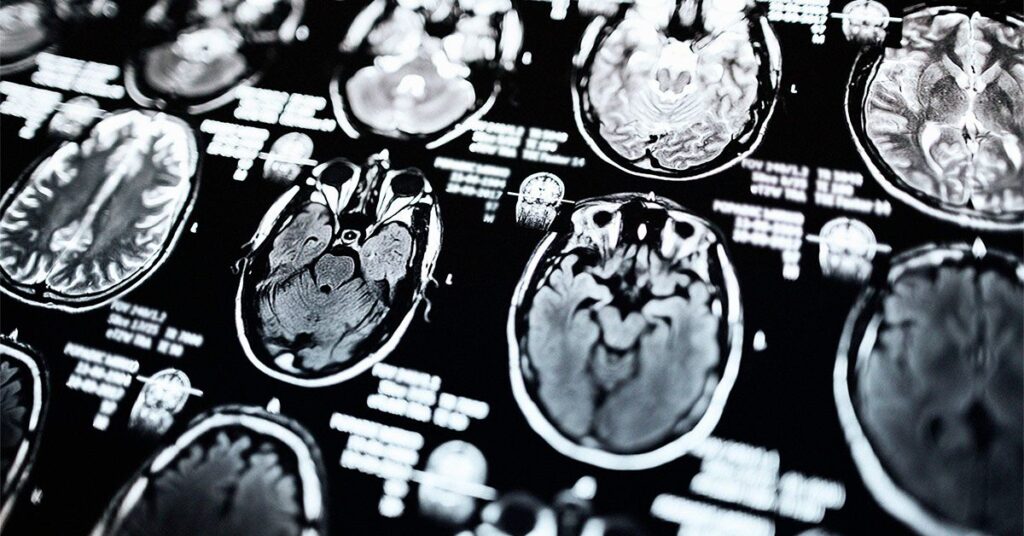

- Scientists may be able to predict disease progression in people with Parkinson’s disease using MRI scans.

MRI scans may help map the functional and structural connections in the brain and allow scientists to predict patterns of atrophy in people with Parkinson’s disease, according to a study published today in Radiology, a journal of the Radiological Society of North America.

In their study, researchers used MRI data from 86 people with mild Parkinson’s disease and 60 healthy controls to map the brain’s neural connections.

They said this information could help them develop an index of disease exposure and predict brain atrophy.

The researchers reported that having Parkinson’s disease for one and two years correlated with atrophy at two to three years past the baseline. Additionally, the models developed by the researchers were able to predict gray matter atrophy accumulation over three years in certain parts of the brain.

The researchers suggest the findings support the theory that functional and structural connections between brain regions could significantly contribute to the progression of Parkinson’s.

The scientists also indicated that the study results suggest that MRI scans could play a role in preventing or delaying disease progression. The researchers suggest that medical professionals incorporate individual-specific information into the model for optimal effectiveness.

“The most significant takeaway of the study is that the brain’s structural and functional connectome significantly influences gray matter atrophy progression in early Parkinson’s disease,” Massimo Filippi, a senior author of the study and a professor of neurology at the Università Vita-Salute San Raffaele in Italy, told Medical News Today. “The study shows that disease exposure indexes, based on healthy brain connectivity and atrophy severity in [Parkinson’s] patients, can predict future atrophy in specific brain regions. This suggests that connectome mapping could be a valuable tool for understanding and predicting the progression of neurodegenerative changes in [Parkinson’s].”